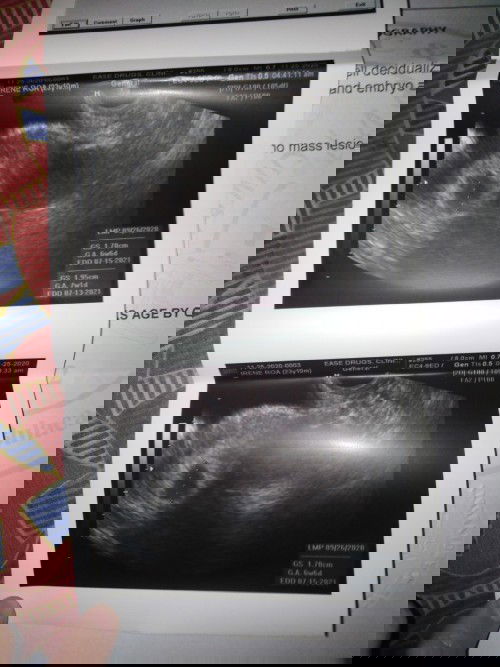

7 weeks Pregnant but still no Heartbeat detected.. Normal lang po ba Yun ๐Ÿ˜Š i have Scheduled 2nd trans V to check the Heartbeat in the 3rd week of dec. #1stimemom #firstbaby #advicepls

Yup thatโ€™s possible ako yesterday first trans v ko @9weeks fetus like na sya and my heartbeat na ๐Ÿ™๐Ÿปโค๏ธ